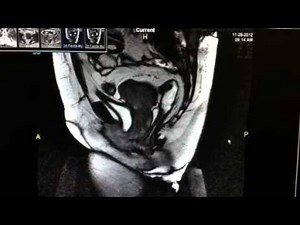

Exam - Proctogrammri

Proctogram - Dynamic Pelvic

MRI - MRI with

Defecography - Pelvic

MRI - Defecating